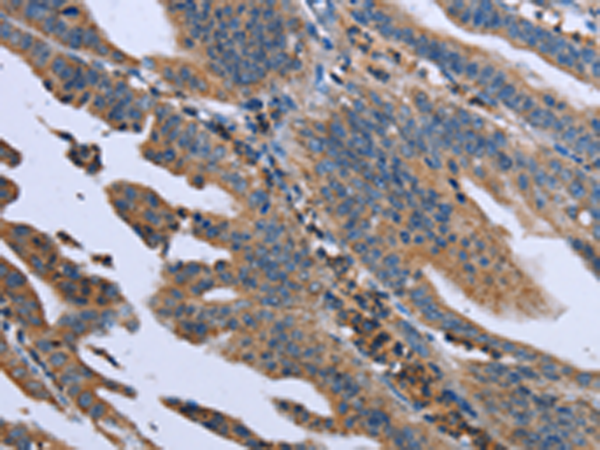

分类: 科研抗体货号: P08352别名: MYD118; GADD45BETA应用: IHC反应种属: Human, Mouse